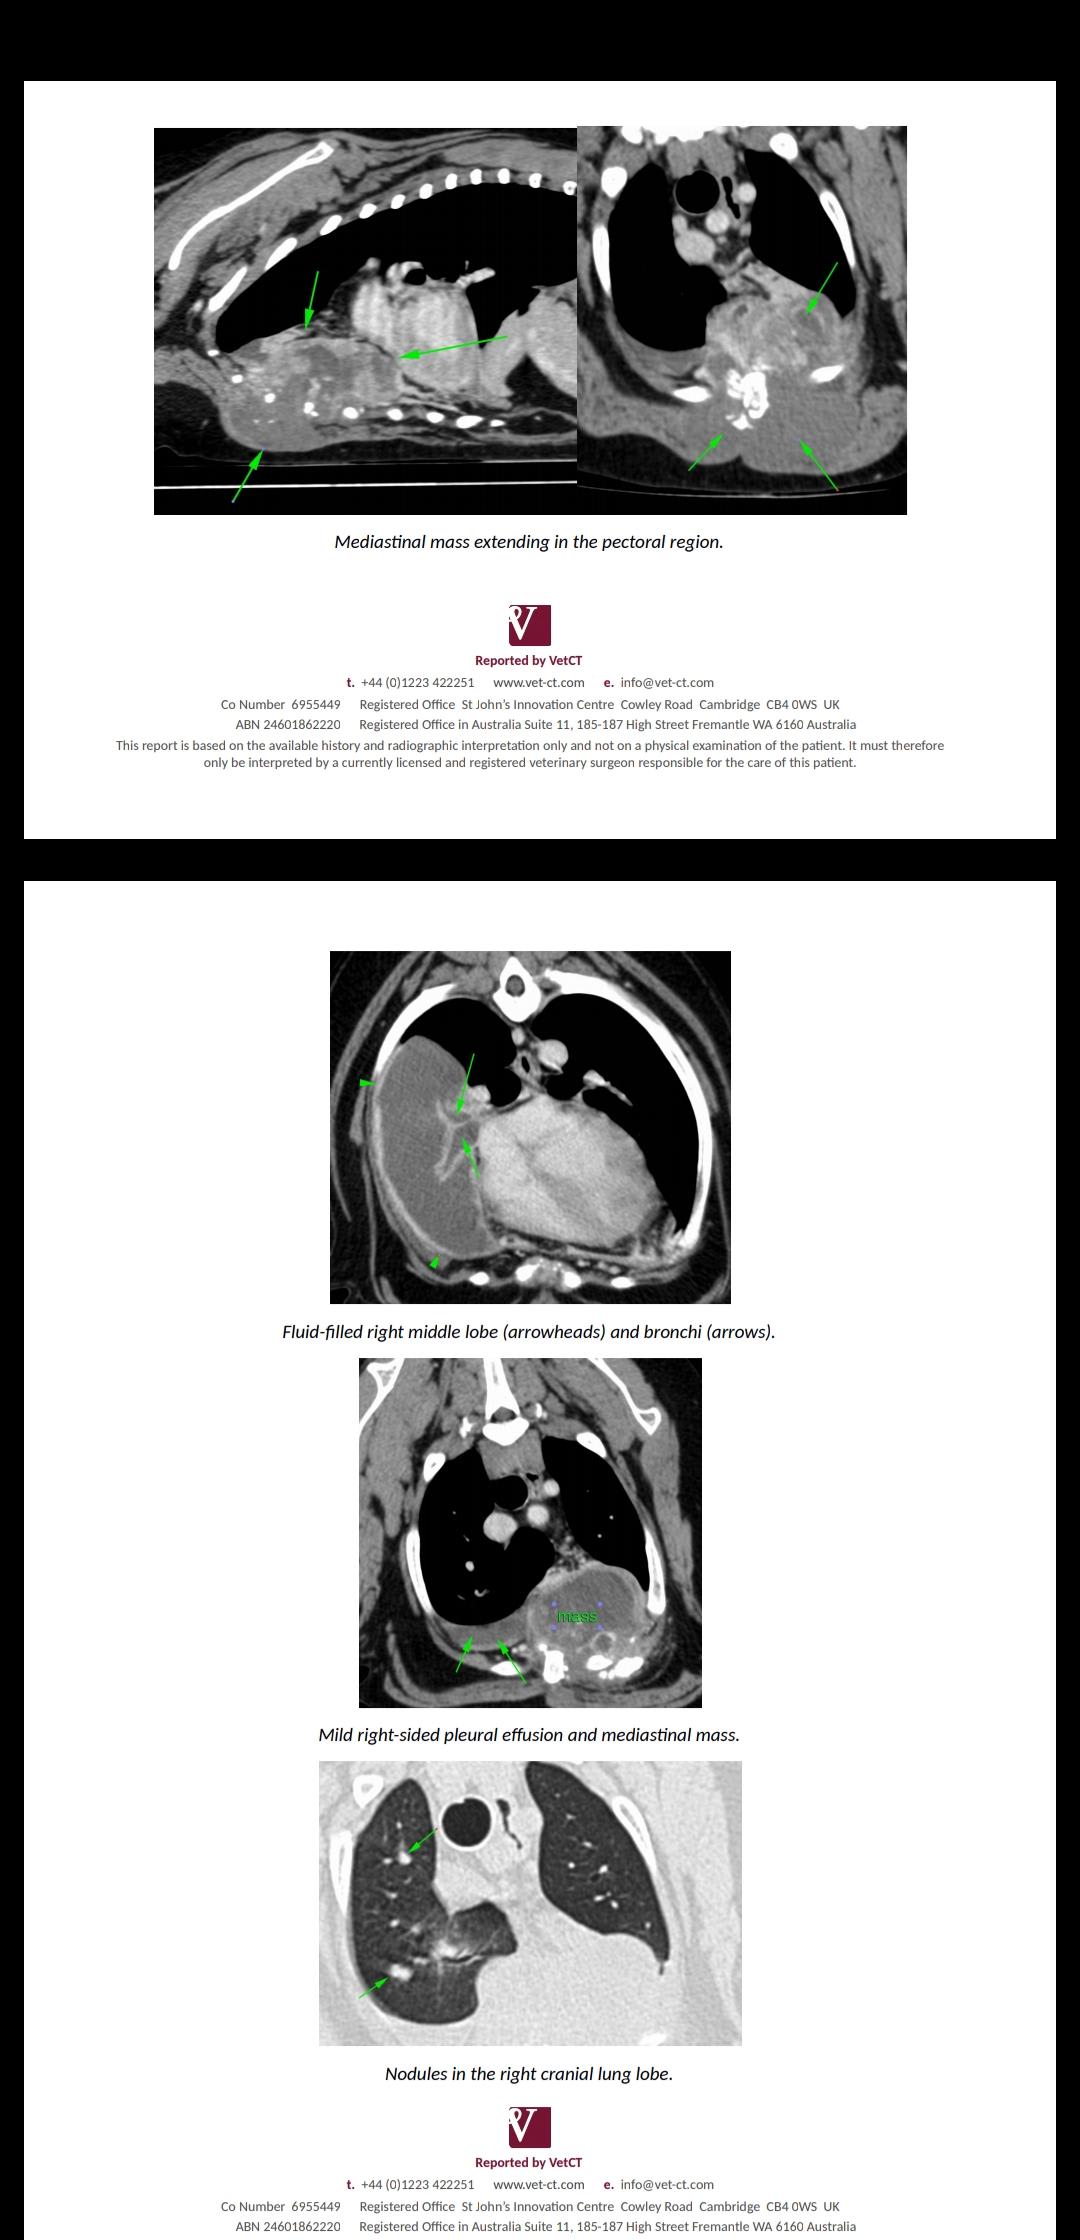

We have had X rays and a CT scan and likely that he has cancer. We have decided to leave him untreated now as he is happy, comfortable, eating and enjoying his walks still. Being prodded by vets was making him very distressed. With our decisions please could you tell us what to expect with his comfort and timeline. Many thanks

Poor Yogi! This is such a tough situation. His timeline turly depends on how comfortable he continues to be and how quickly this mass grows and spreads. I would expect that he may only live for a few months since it looks like there are some nodules in the lungs and the mass currently looks pretty big already. The key is to make sure he stays on pain meds as he needs them and don't be afraid to give him the high end of his dose of meds if needed. The key is to keep him comfortable until he has a poor quality of life and at that time, you may choose humane euthanasia. I hope this helps and my thoughts are with you.